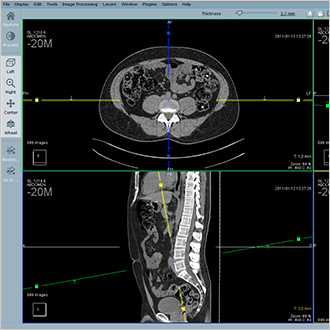

Hyper.PACS

HyperPACS is an universal PACS for all medical images, both DICOM and non-DICOM. It is based on three main pillars: speed, stability and security. Hyper.PACS provides fast data access, stability and 100% data security.

The interface has been developed in collaboration with users to be intuitive for diagnosis, visualisation and telemedicine. Workflow is optimised with hanging protocols, history display and session parking.

Additional modules such as orthopaedic planning, telemedicine image exchange are available.